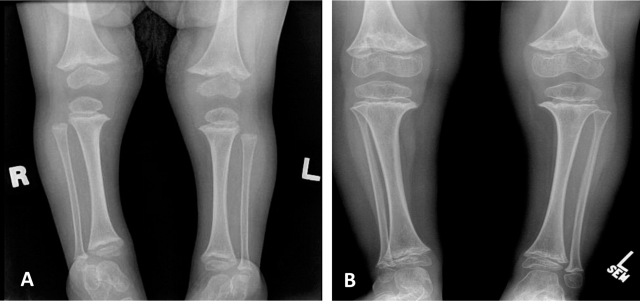

Fig.3. Radiografia das extremidades inferiores de criança com 2 (A) e 4 (B) anos de idade mostram alterações metafisárias típicas e lucências císticas irregulares de margens escleróticas e aparência fragmentada.